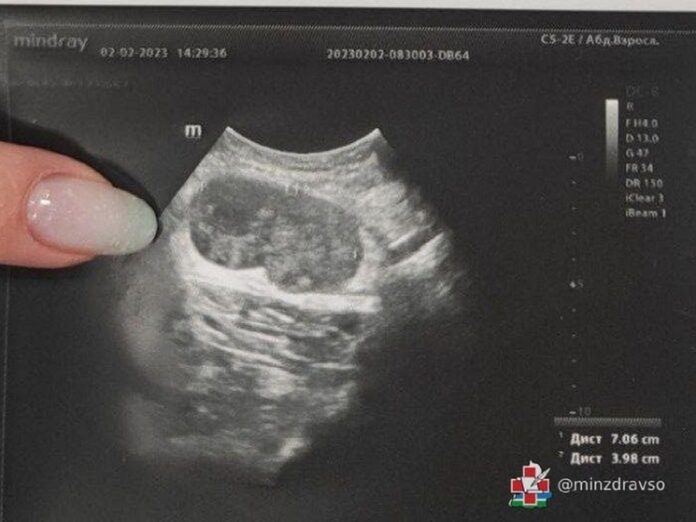

В ЦГКБ №3 Екатеринбурга зафиксирован необычный медицинский случай: у 63-летнего пациента диагностировали метастаз меланомы, хотя первичный очаг опухоли обнаружить не удалось. Мужчина обратился в клинику с жалобой на уплотнение в подмышечной области, которое при ультразвуковом исследовании оказалось увеличенным лимфоузлом размером 70/40 мм.